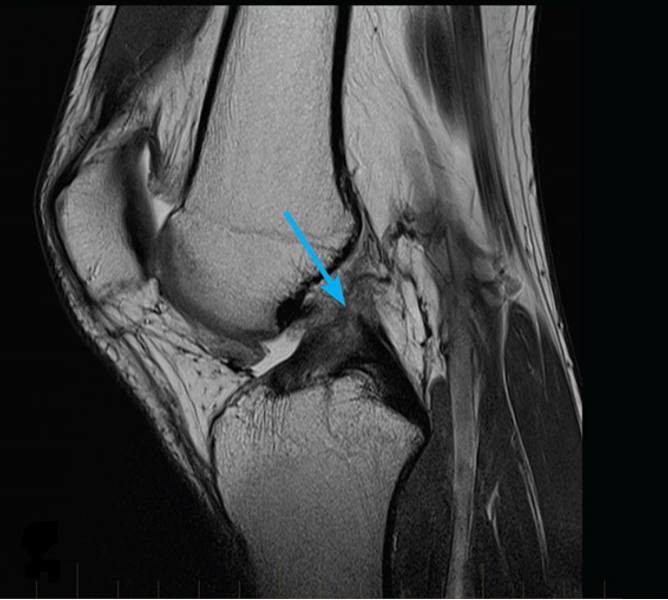

Показания для проведения МРТ коленного сустава:

- переломы;